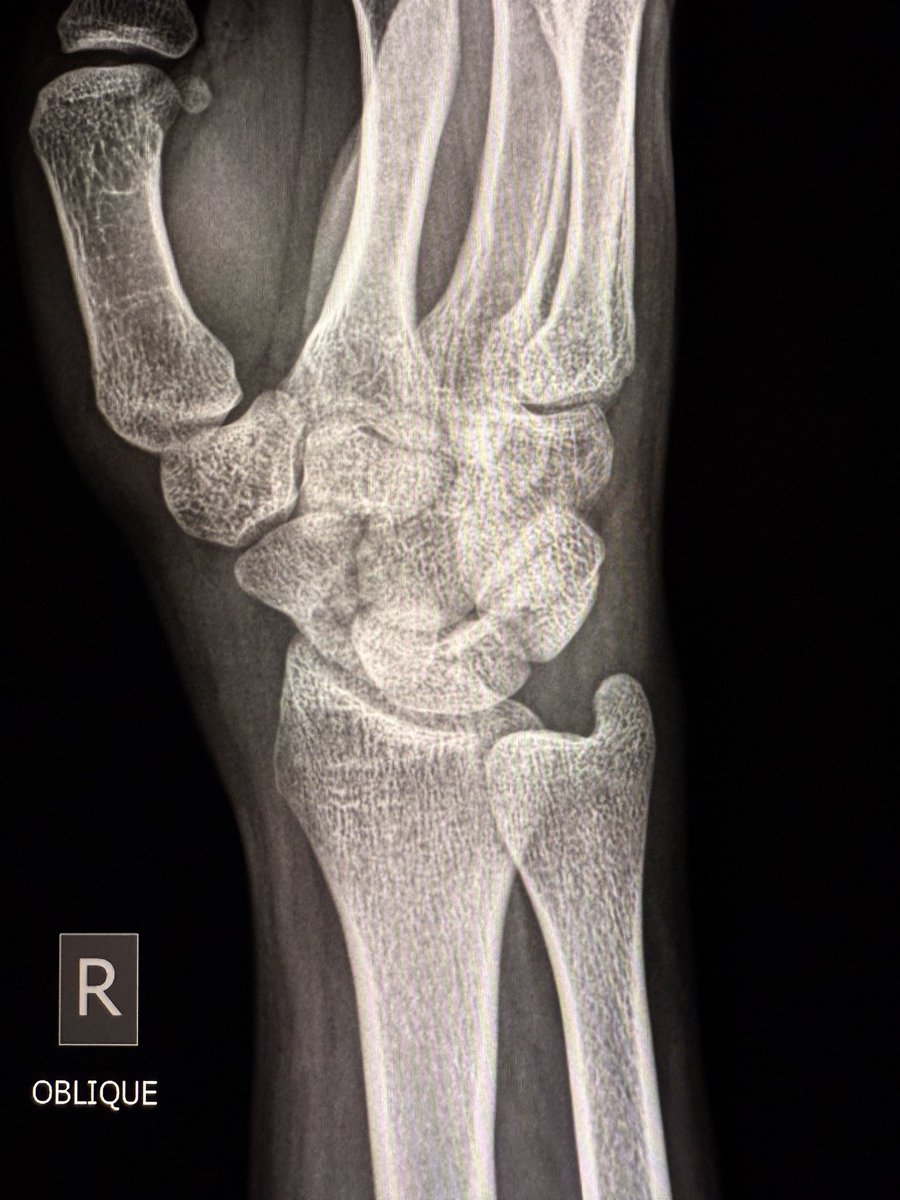

A large dorsal talar beak on sagittal CT or lateral ankle radiograph.

Talar beak is a marker of restricted subtalar motion, not a diagnosis. In a young patient, actively search for a subtalar coalition.

This case showed a fibrous coalition of Medial accessory talocalcaneal articulation at the level of the posterior sustentaculum tali, between the Talus and Calcaneus.

Wisdom: A talar beak should trigger a search, not end it.